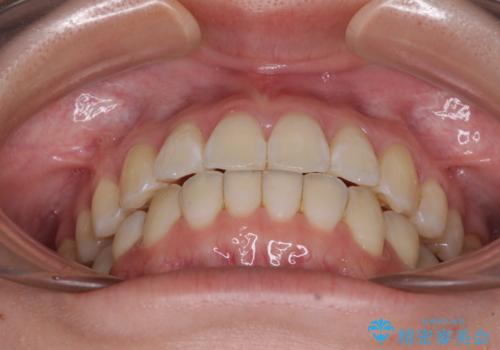

- 海外留学の予定があるが、学生のうちに歯列を整えたいとのことで来院された患者様です。

前歯にデコボコがあり、口元がやや突出した印象があったため、IPR(歯と歯の間を削る)と親知らずを抜歯した上での歯列全体の後方移動をメインに、インビザラインを用いて矯正治療を行うこととしました。

年に一度、夏休みの時期にしか帰国できないため、帰国のタイミングに合わせてマウスピース交換スケジュール治療計画としたため、3年半という期間を要しました。

留学先でもしっかりとマウスピースの装着を実践してくださったので、ご本人の満足のいく仕上がりとなりました。